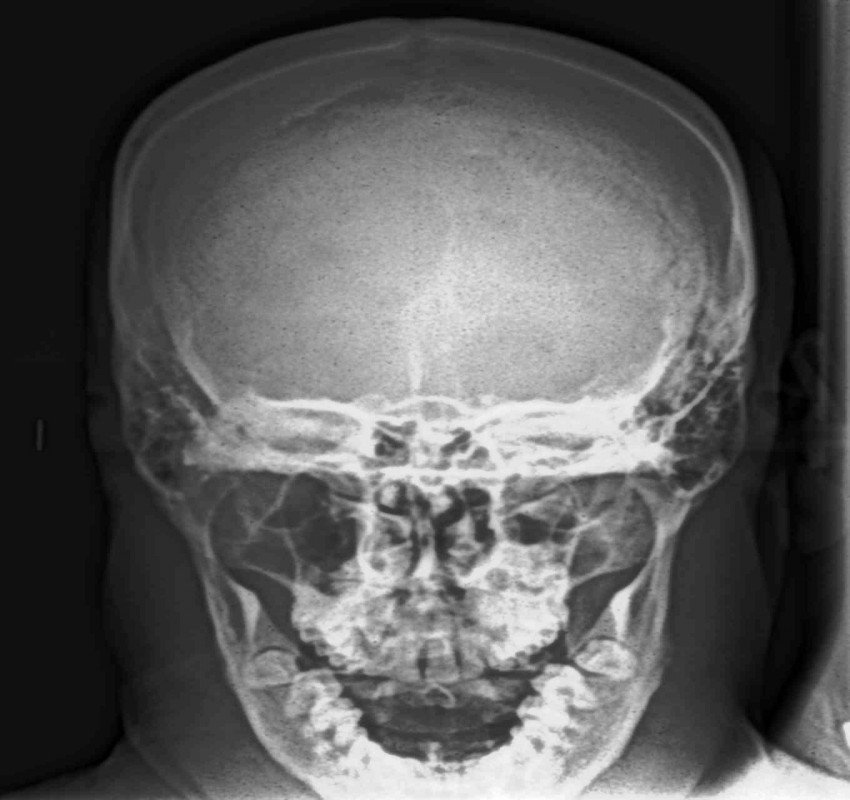

Dentistry has witnessed tremendous advances in all its branches over the past three decades. With these advances, the need for more precise diagnostic tools specially imaging methods has become mandatory. From the simple intraoral periapical x-rays, advanced imaging techniques like computed tomography, cone beam computed tomography, magnetic resonance imaging and ultrasound have also found their place in modern dentistry.

Changes from analouge to digital radiography has not only made the process simpler and faster but also made image storage and manipulation and retrieval easier. The 3- D imaging has made the complex craniofacial structures more accessible for examination.